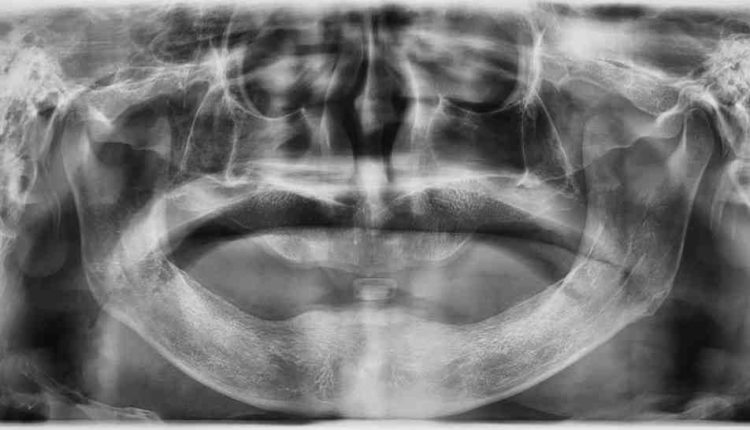

Dental bone grafting is actually a relatively small procedure. Your dentist will make an incision to uncover your jaw bone, then inoculate new bone material with it. This may interest you : Dental Implant Reviews. Your bone creates new bone cells around the grafted material, and builds bone exactly where they need it.

There are several ways dental bone grafting can be done, but the basic procedure is the same: A dentist or oral surgeon makes an incision in the jaw and grafting (sticking) other bone material to the jaw. See the article : Cost Of Dental Implant. Dental bone grafting is usually done if someone has lost one or more adult teeth or has gum disease.